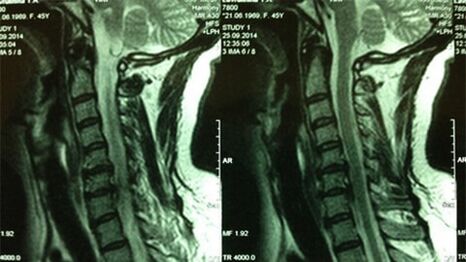

- Servikal Departman X -Ray; Sürecin ilk aşamasında, servikal departmanın MRG'si daha bilgilendirici olacaktır - katı ve yumuşak dokuların yüksek kaliteli görselleştirilmesini sağlayacak - intervertebral disklerin durumunu, osteofitlerin varlığını, deformasyonları, sinir köklerine ve kan damarlarına zarar verecek; bağların, kasların, kemik dokusunun durumunu değerlendirecektir;